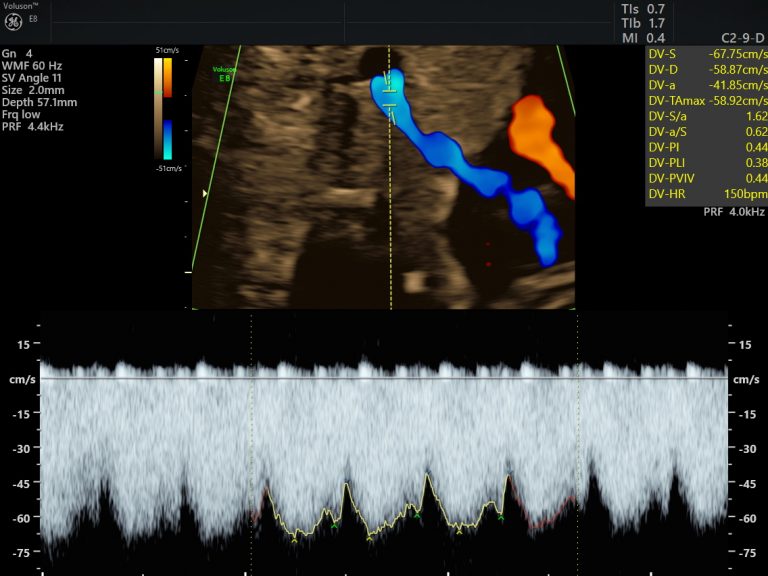

Small for gestational age babies are identified by obstetricians and referred to us for Growth and Doppler studies. This means we evaluated the adequacy of blood flow between the mom and placenta, baby and placenta as well as the flow into the baby’s brain. This information helps to plan the surveillance and delivery plan for the smaller baby meticulously. One always need to measure up the risk of being small intra-uterine, versus the risk of neonatal complications due to preterm delivery.